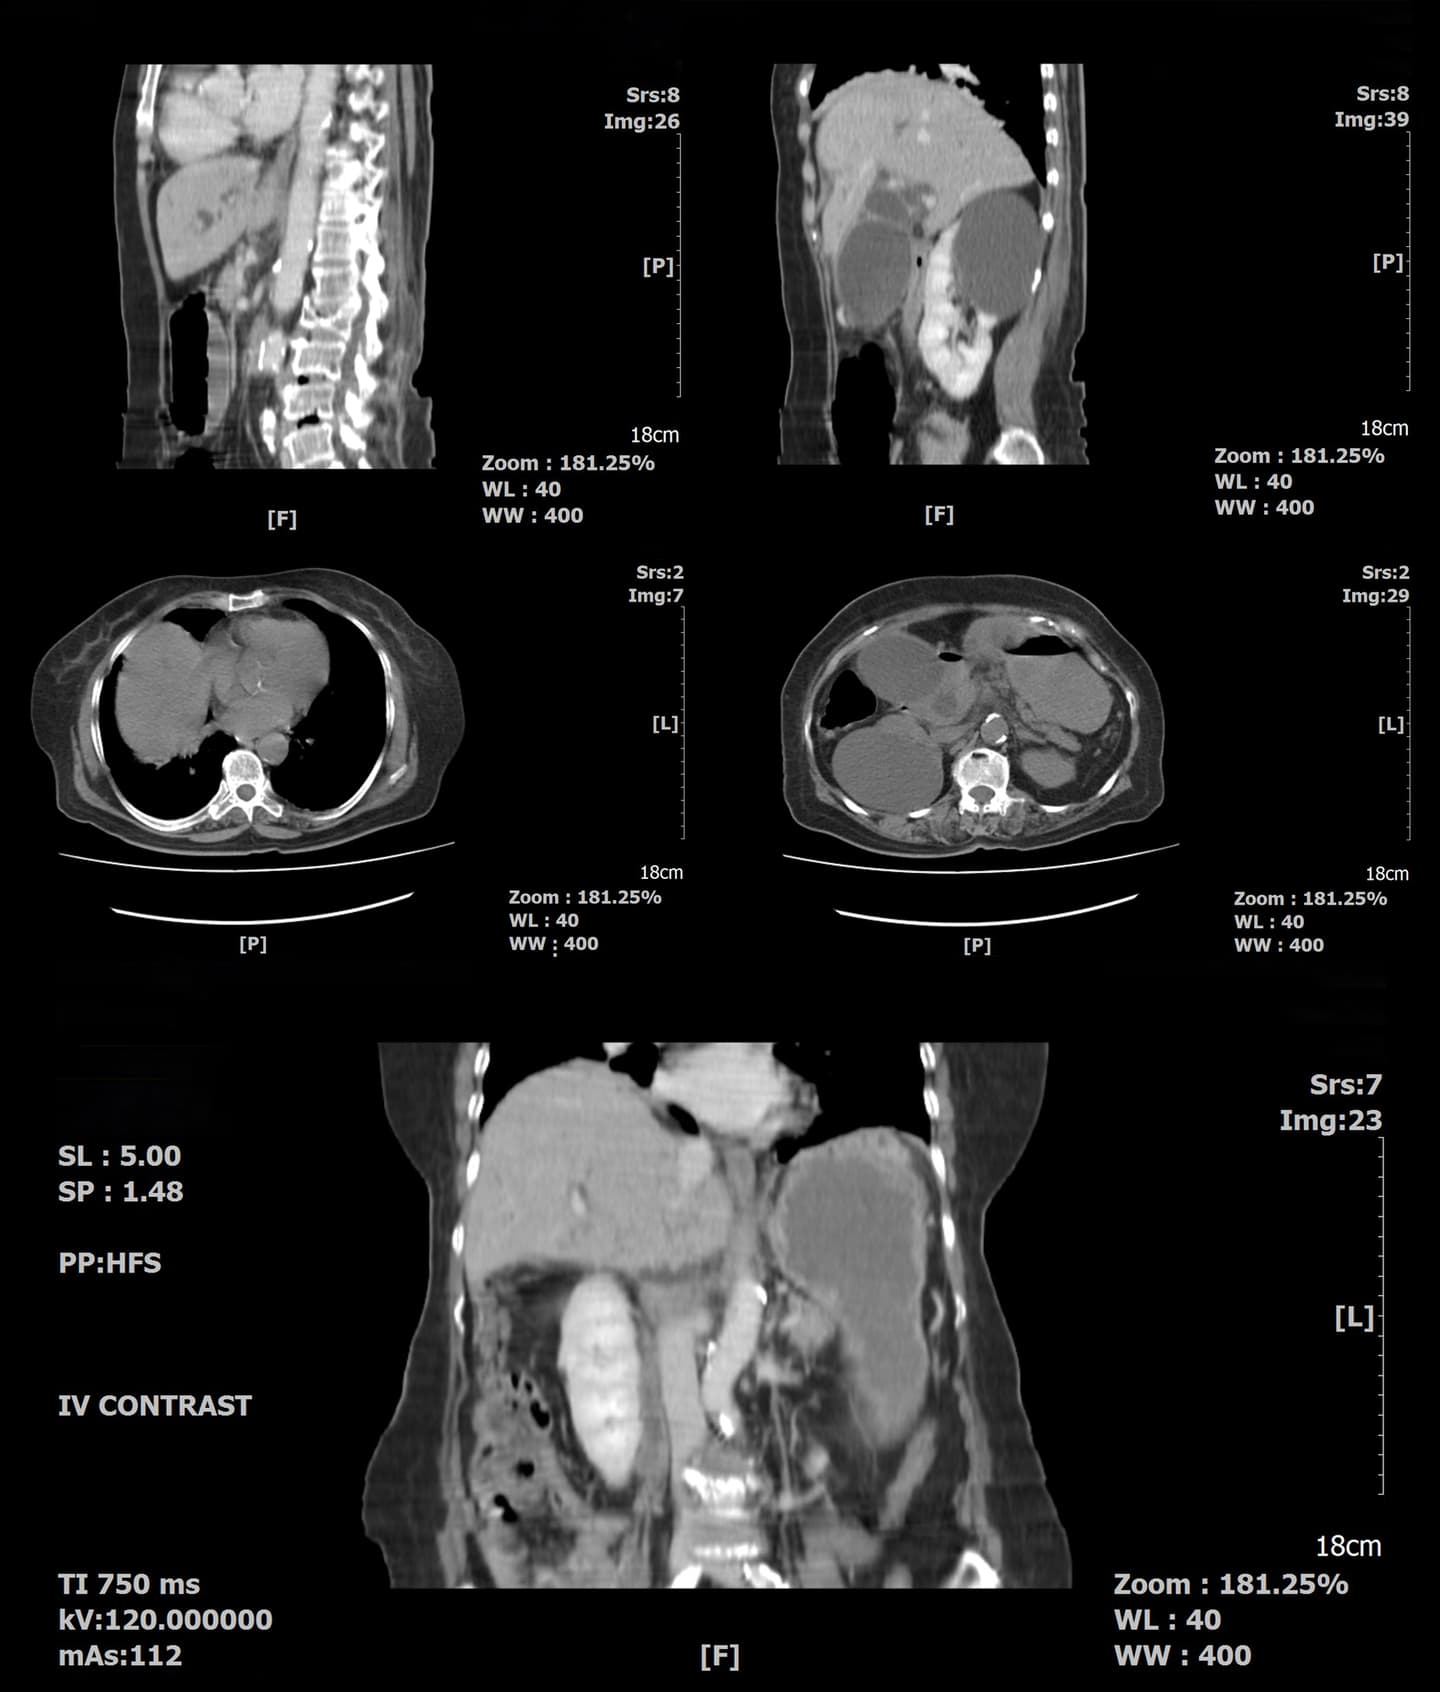

実際に撮影したCT画像です。各臓器が細かく写るので、詳細な情報を得ることができます。